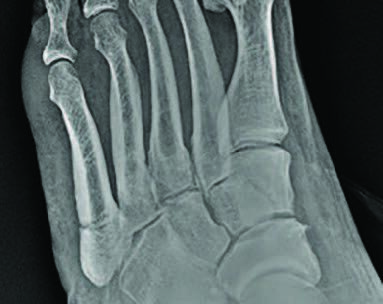

Zone 2 fractures are Jones fractures, located 1.5 cm proximal to the tuberosity, extending into the fourth and fifth intermetatarsal joint (see second photo above). This fracture is more severe due to tenuous blood supply at the metaphyseal-diaphyseal junction.4-6 Smith and team studied 10 fresh frozen cadaver specimens following arterial injection of India ink or barium sulfate, and reported that metatarsal blood supply arises from the nutrient artery, metaphyseal perforators, and periosteal arteries. They noted a watershed area between the nutrient artery and the metaphyseal perforators, corresponding to an area of poor healing as the nutrient artery terminates at the proximal diaphysis and metaphyseal vessels supply the tuberosity.1,5 Dameron reported a non-union rate of 25 percent in this fracture pattern.7